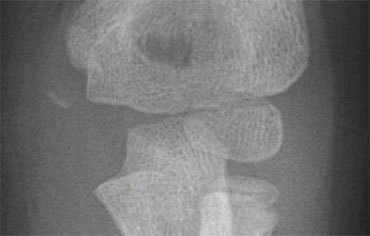

Lateral condyle fracture. On the x-ray only a small metaphyseal fragment is visible. The detatched fragment however is larger than it appears on the radiograph. The fracture extents into the lateral ridge of the trochlea. Elbow is probably unstable. Lateral condyle fracture. On the x-ray only a small metaphyseal fragment is visible. The detatched fragment however is larger than it appears on the radiograph. The fracture extents into the lateral ridge of the trochlea. Elbow is probably unstable.

Lateral Condyle fractures (4) .

Since most of the structures involved are cartilageneous, it is very difficult to know the exact extent of the fracture.

Sometimes the fracture runs through the ossified part of the capitellum. In those cases it is easy.

The case on the left shows a lateral condyle fracture extending through the ossified part of the capitellum.

This is a Milch I fracture. The elbow is stable.

There is too much displacement so osteosynthesis has to be performed.